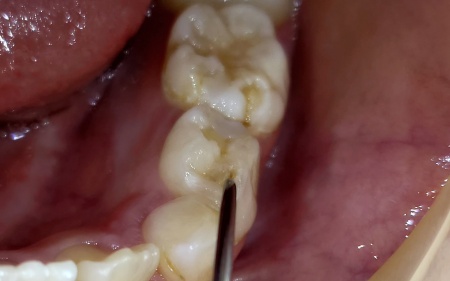

8歳女の子 左下奥歯の虫歯をコンポジットレジンで修復した症例

拝見したところ、左下奥の乳歯の噛み合わせ面にある細い溝に黒ずんだ変色が認められました。

痛みなどの自覚症状はなかったものの視診に加え細い器具で触診を行ったところ、溝部分に約2mmほど器具が沈み込む感触がありました。

歯の表面にある小さな入り口から、歯ブラシの届きにくい内部へ向かって虫歯が広がっている可能性が考えられます。

噛み合わせの溝は非常に細く深いため、大きな変化がないように見えても気づかないうちに内部で虫歯が進行してしまうことがあります。

見た目以上に内部で虫歯が進行していたため、健全な歯質をできるだけ残しながら感染部位を慎重に取り除きました。